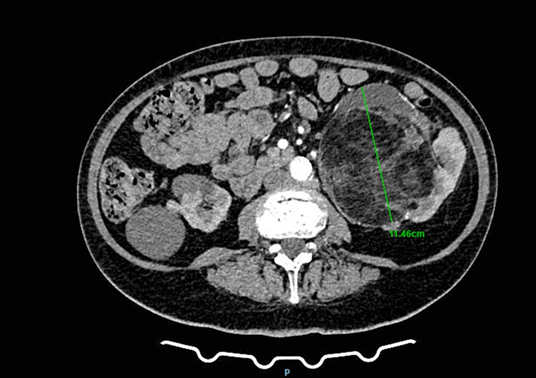

A 78-year-old woman presented to a urology clinic with intermittent left flank discomfort persisting for approximately six months. She denied hematuria, dysuria, or a history of urinary tract infection and renal inflammation. Laboratory findings revealed mild anemia (hemoglobin 109 g/L, hematocrit 0.323 L/L) and normal renal function (creatinine 90 µmol/L, urea 7.7 mmol/L). Her medical history was notable for hypertension and well-controlled type 2 diabetes mellitus managed with oral hypoglycemics. On physical examination, a palpable mass was detected in the left flank and hemiabdomen. Abdominal ultrasonography revealed a poorly defined lesion within the left kidney, approximately 90 × 60 mm in size. Contrast-enhanced CT of the thorax, abdomen, and pelvis demonstrated multiple small cystic lesions up to 25 mm in the left kidney, along with two major solid masses of clinical significance. A lobulated mass at the upper pole (67 × 60 mm) exhibited central calcifications and contrast enhancement consistent with RCC (Figure 1). A second, well-circumscribed lipomatous lesion (110 × 100 mm) was identified at the lower pole and renal hilum (Figure 2), causing compression and deformation of the collecting system without invasion, initially interpreted as an angiomyolipoma. The renal vein demonstrated a retroaortic course, a relevant anatomic variation for surgical planning. After multidisciplinary evaluation including urologists, oncologists, abdominal surgeons, and interventional radiologists, preoperative embolization of the left renal artery was recommended, followed by radical nephrectomy.

Figure 2: CT image showing a giant liposarcoma occupying the lower pole of the left kidney.